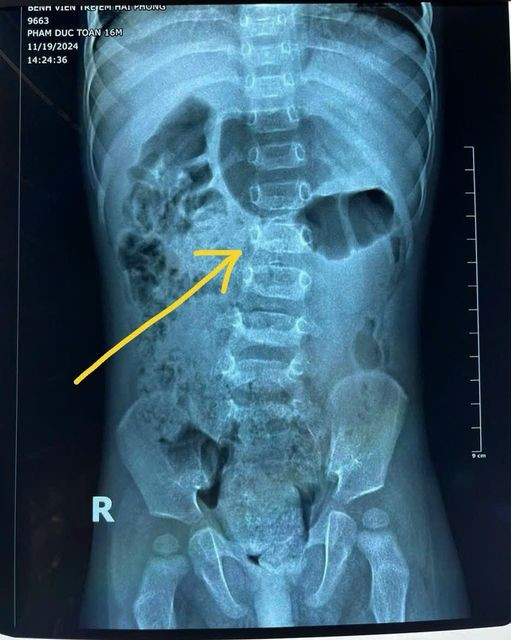

| Hình ảnh phim chụp của bệnh nhi 16 tháng tuổi bị cong vẹo cột sống thắt lưng. Ảnh: BVCC |

Điều đáng lưu ý là ở giai đoạn này, cơ cạnh cột sống thắt lưng của trẻ còn yếu, không đủ sức nâng đỡ cột sống một cách vững vàng. Trong một số trường hợp, trẻ còn bị giảm cơ lực toàn thân, đặc biệt là bên trái, kết hợp với tình trạng tăng trương lực cơ. Khi trẻ phải ngồi lâu trong tư thế không tự nhiên, cột sống bị áp lực lớn dẫn đến tình trạng cong vẹo nghiêm trọng.

Khi cơ lực của cơ cạnh cột sống thắt lưng chưa đủ khỏe, chúng không thể nâng đỡ cột sống tốt. Đồng thời, bệnh nhi này có cơ lực toàn thân giảm đặc biệt bên trái và tăng trương lực cơ toàn thân bên trái. Hơn thế, người nhà cho con ngồi quá sớm và lâu khiến cột sống thắt lưng trẻ cong vẹo.